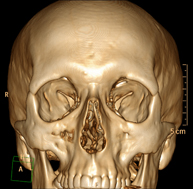

- Facial mass CT

Radiological test that provides high definition anatomical images of the facial mass (face) using CT (Computed Tomography) equipment. Indicated for: tumours, plastic surgery.